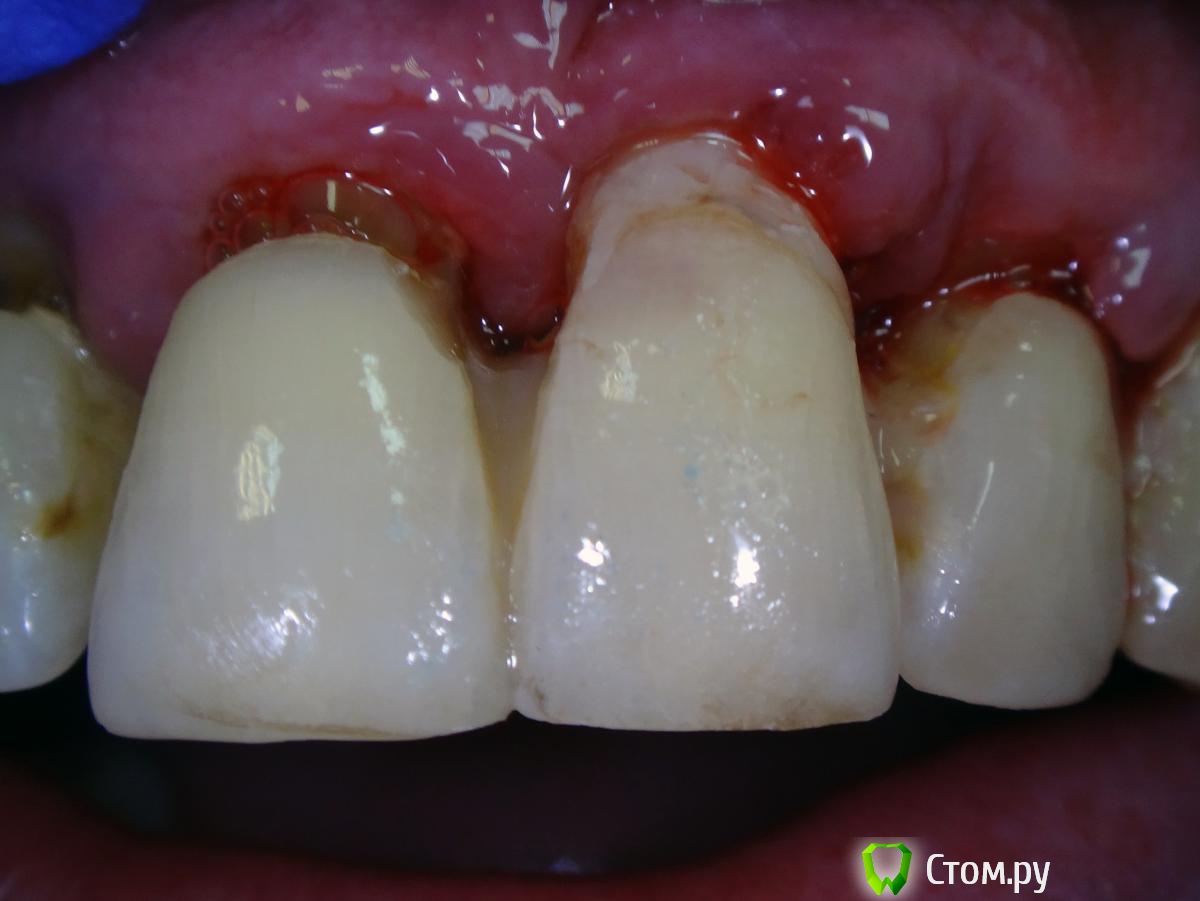

Kalipso Опубликовано 28 августа, 2014 Поделиться Опубликовано 28 августа, 2014 Я ставлю сразу после удаления .1 . Снимаю слепок до удаления , и прошу техника либо сделать коронку или wax up после чего по ключу сама изготавливаю .2. Удаляю .3.Жидкотекучим креплю коронку . Как- то так . Это наверно самая моя первая такая работа .http://s017.radikal.ru/i432/1408/7c/d61e22c1c7ae.jpg http://s018.radikal.ru/i519/1408/d2/23c0aebcd1b4.jpg http://s016.radikal.ru/i336/1408/51/3ede7c77a5d0.jpg http://s41.radikal.ru/i091/1408/cc/604419754cb7.jpg 3 Ссылка на комментарий

Kalipso Опубликовано 28 августа, 2014 Поделиться Опубликовано 28 августа, 2014 Спасибо за кейс. Сразу после удаления крепите или ждете какое-то время? Жидким крепите с протравливанием/бондом соседних зубов? Не возникает ли потом сложностей как снять это? Есть ли промывное пространство между десной и временной коронкой или клеете впритык?1.Удаление, гемостаз.2.бонд , коронка.3.все ок, иногда раньше времени слетает .4.не знаю правильно или нет но клею впритык . Проблем не было . 1 Ссылка на комментарий

Slaggy Опубликовано 11 сентября, 2014 Поделиться Опубликовано 11 сентября, 2014 (изменено) Если планируется удаление переднего зуба, то стараемся одномоментно установить имплантат. Если это невозможно или нельзя нагружать винт, то делаем адгезивный "мериленд". Если пролёт в несколько зубов, то только съёмное. Можно дополню?Если пролет в несколько зубов, но ограничивающие деффект зубы будут обтачиваться, то можно армировать времянки металлом.вторую фотку перезагружаю:Это как раз на 3-4 день овоиды сделаны. первая фотка на 3-4 день после 3-4 дня после удаления.Что скажите мне изменится в поверхностных слоях сгустка и окружающих их тканей за 3-7 дней? Прорастет чем? или что?Нифига не вижу разницы одномоментно или на 3 день. Ааа. Есть разница. Не кровит и можно работать.А еще пациент осознав потерю значимей оценит обретение. Если удаляемый зуб имеет коронку, то можно его использовать для времянки.Извините за качество, не успел отфоткать - фотик сдох, успел пару раз нажать на затвор без подготовки.Вся центральная группа с клиновидными деффектами и подвижна, 21 - выдвинут на 3,5 мм. пациент не хочет с ним расстоваться, держит губами, оберегает.Нужен был быстрый "ход конем", чтоб он на шею не сел. Я пообещал за час сделать лучше чем есть. Пальцами удалил 21, обрезал под овоид, ретроградно запломбировал жидкотекучим, им же залил клиновидный и приклеил, армировав стекловолоконной лентой.Говенная работа, но она позволит мне дальше человека вывести на нормальное лечение.Вообще данный товрисч очень тяжелый, там все под бульдозер, а потом...Еще рас сорри за жесть, но это жизнь, работа, будни ))))) Изменено 11 сентября, 2014 пользователем Slaggy Ссылка на комментарий